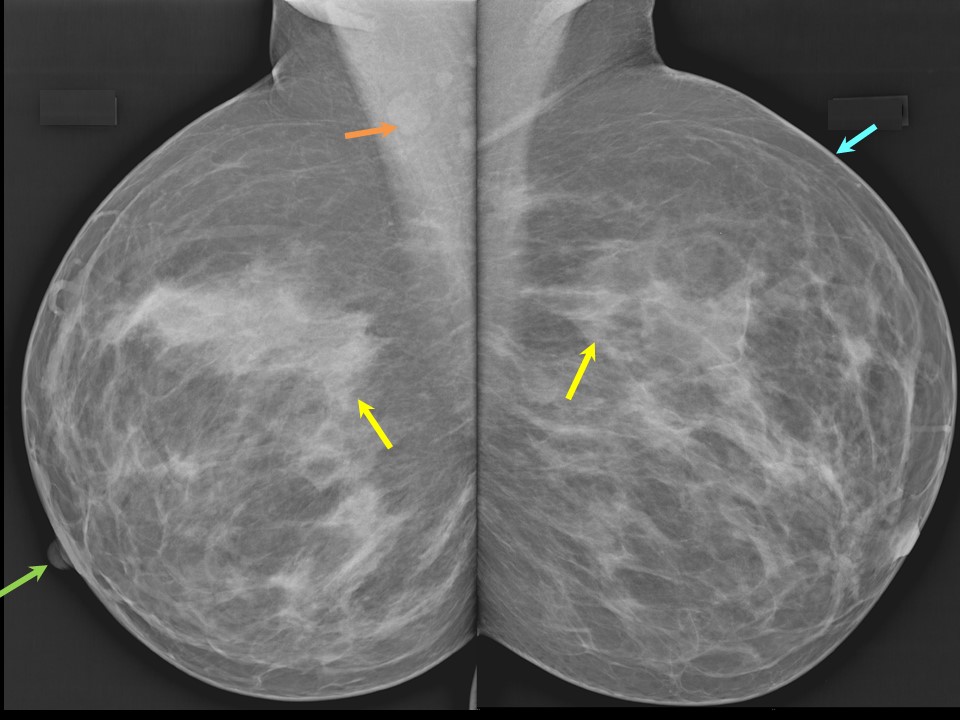

Что такое маммография: важность, процесс и результаты

Раздел: Необычные решения